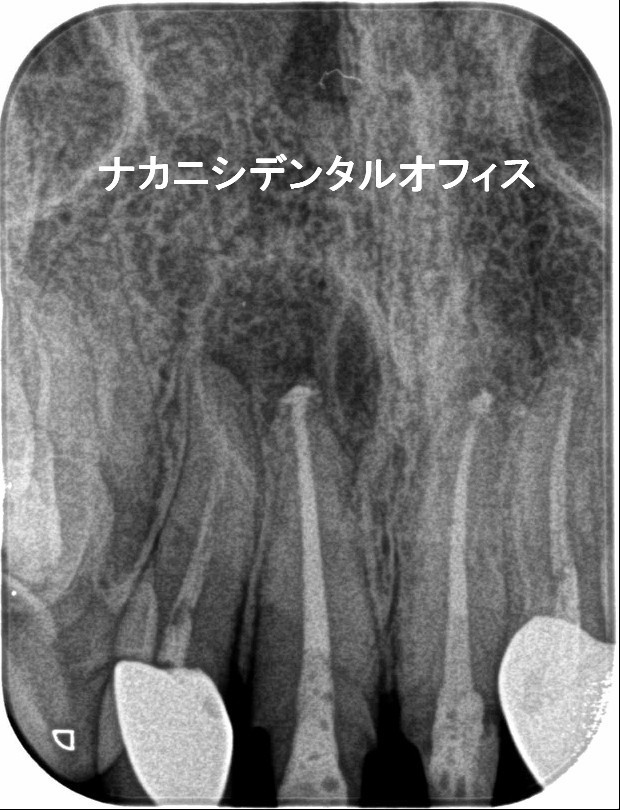

初診時に左上奥歯に冷痛と咬合痛で来院。3年前より、痛みがあったがどこに行っても原因がわからず。マイクロスコープ下で診断したところクラック(ヒビ)がはいっていました。肉眼では確認できず、レントゲンでもわかりませんでした。その日にMTAセメントでクラックを封鎖し経過観察としました。1週間後、冷痛、咬合痛は改善され、神経もとらず温存することができました。

右上の奥歯の痛みと冷水痛で来院されました。かなり神経に近い深い虫歯になっていましたので、年齢や虫歯の状態によりマイクロスコープを使い、MTAセメントで神経の保存を行いました。後日、痛みもしみる感じもなくなり順調に経過をたどっています。